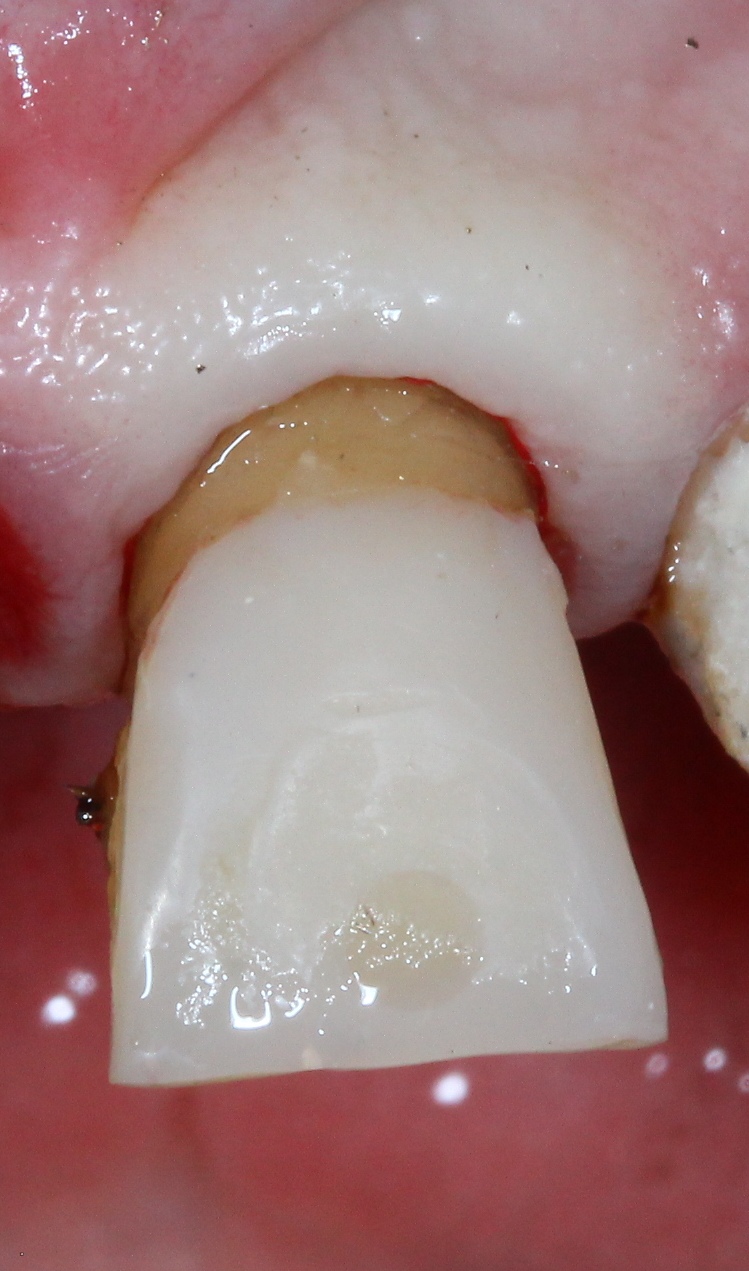

Extrusion unbeschliffen Veröffentlicht 16. März 2012 am 749 × 1271 in Erzeugung eines Ferruleeffektes durch Extrusion eines Frontzahnes postendodontisch